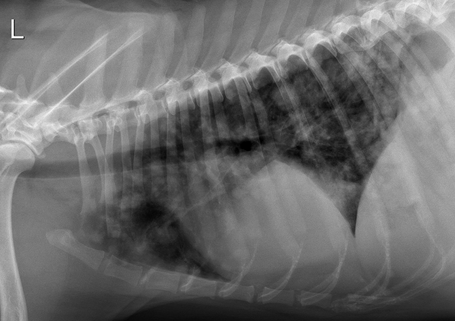

Interstitial pattern

aorta and vena cava is blurry